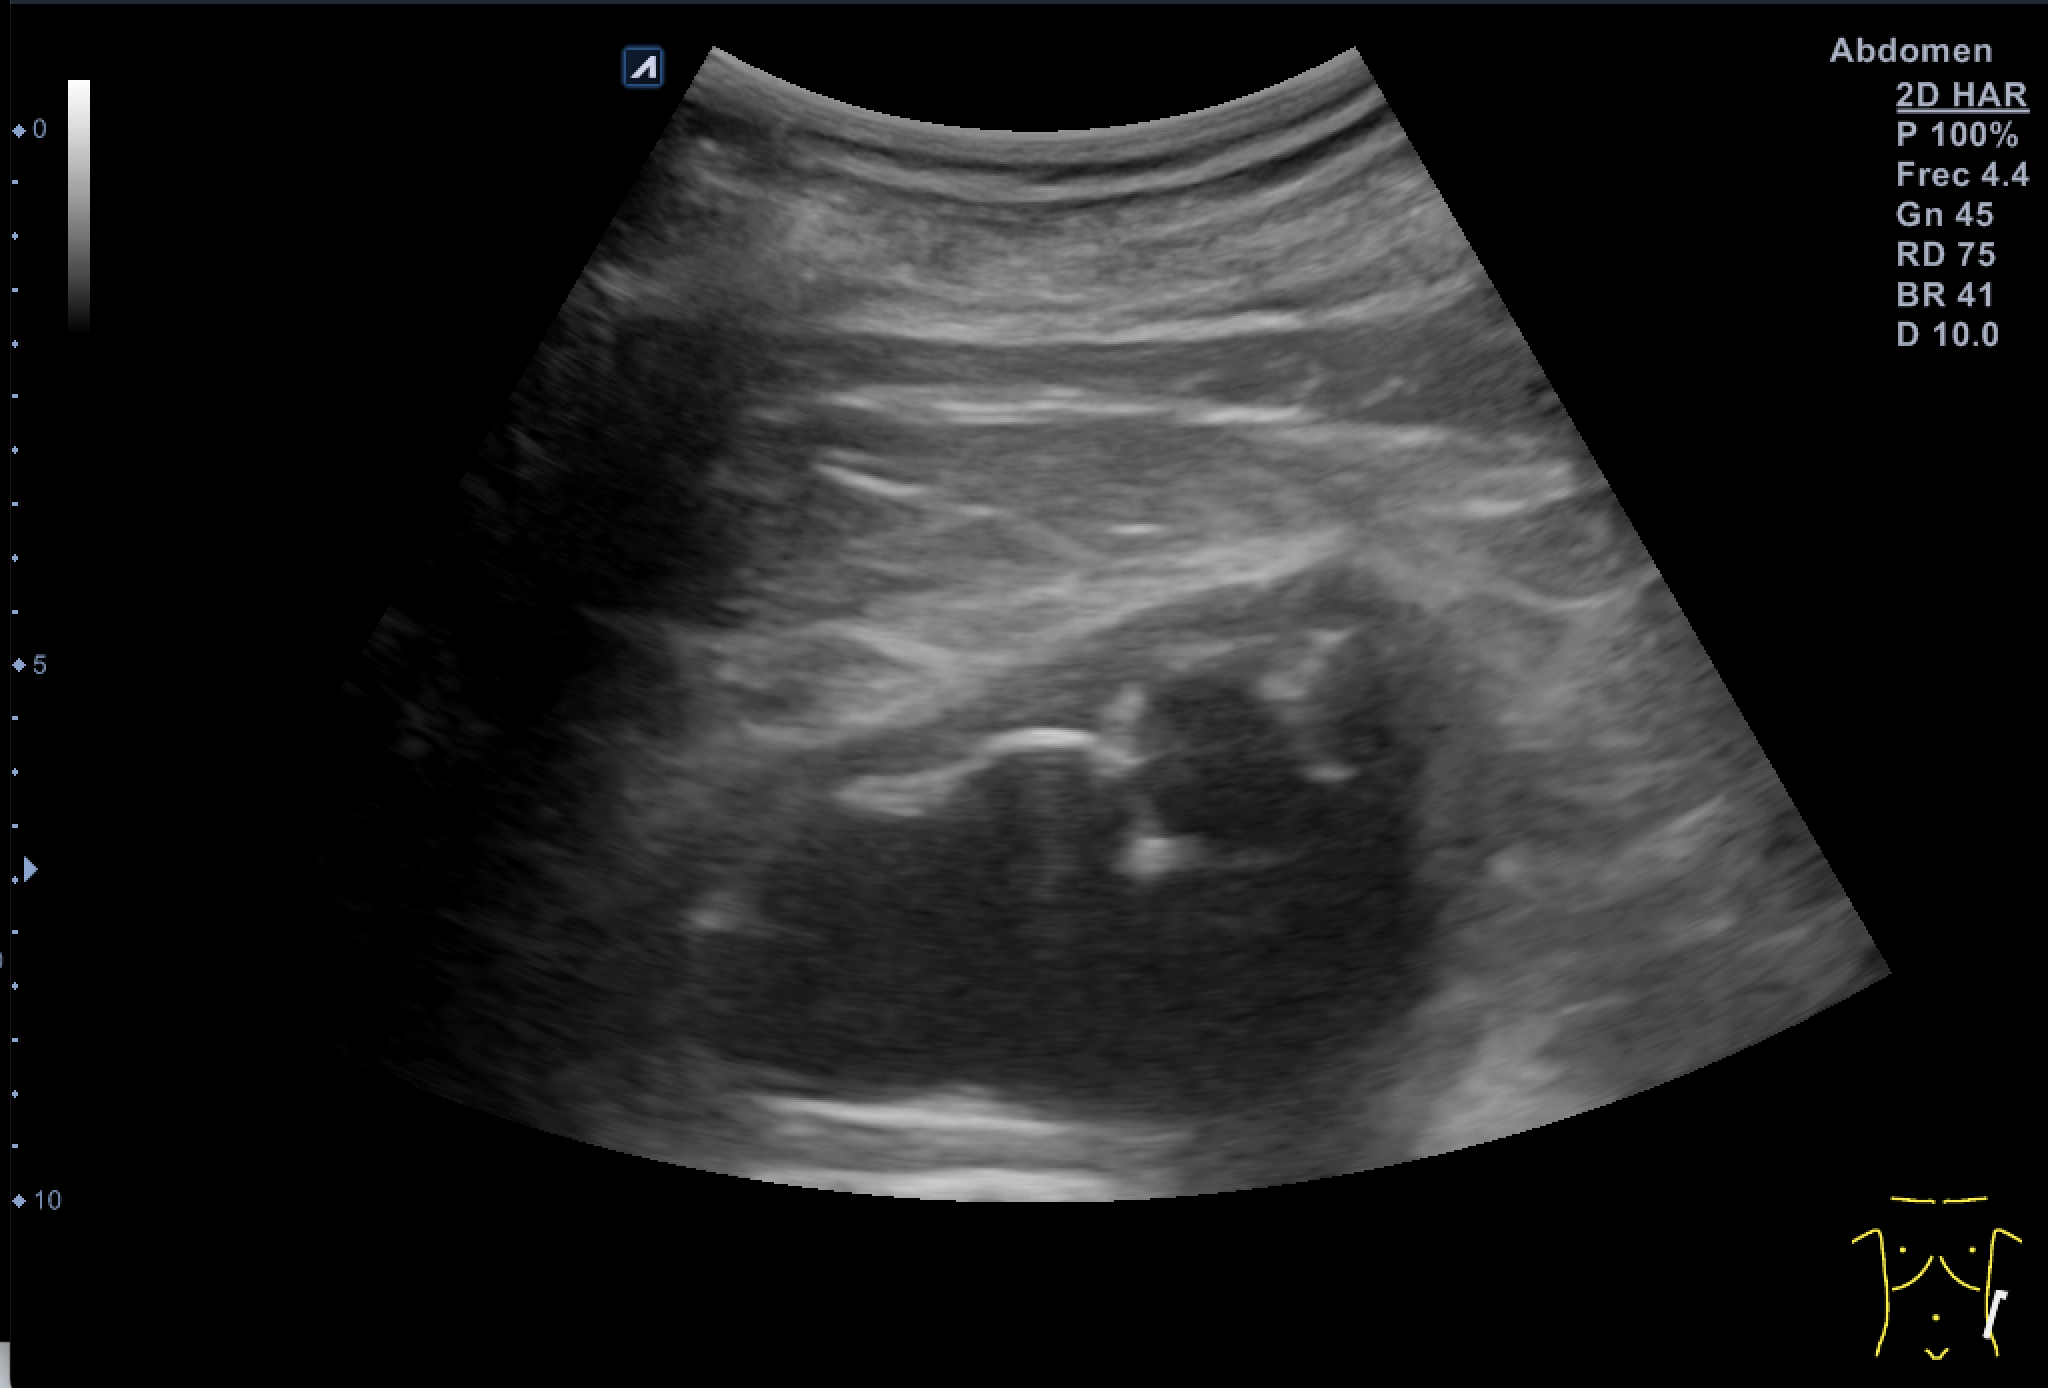

Hallazgos ecográficos

Tras valoración vesicoprostática con vejiga normal, jet vesicales visibles con próstata de 45 cc y residuo postmiccional mínimo. Riñón derecho como normal de tamaño y morfología sin dilataciones pielocaliciales (11 cm de tamaño). El Riñón Izquierdo (RI: 9 cm) presentaba una hidronefrosis grado IV y atrofia cortical con pelvis renal distendida, no consiguiendo detectar la causa obstructiva y considerando la posibilidad de una estenosis de la unión pieloureteral y como segunda opción una litiasis  ureteral pese a la normalidad de los jets vesicales.